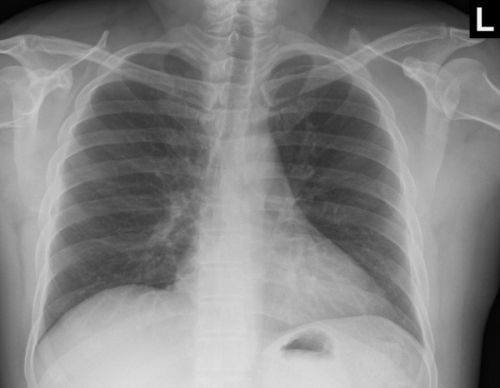

Tool to train medical student's eyes as to what a normal chest x-ray looks like, with over 500 consecutive normal images.